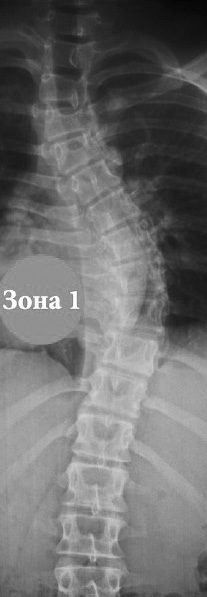

Лечебная физкультура (ЛФК) по методике «Осознанной коррекции сколиоза и нарушений осанки» (ОКС) включала деротационные, ассиметричные, изометрические упражнения, на их долю приходилось около 75% всех упражнений комплекса. Пациенты 10–11 лет обучались «локальному дыханию» по методике К. Шрот (рисунок).

Рис. Обозначение зоны локального дыхания при правостороннем грудном сколиозе.

Fig. The local breathing zone in right-sided thoracic scoliosis.